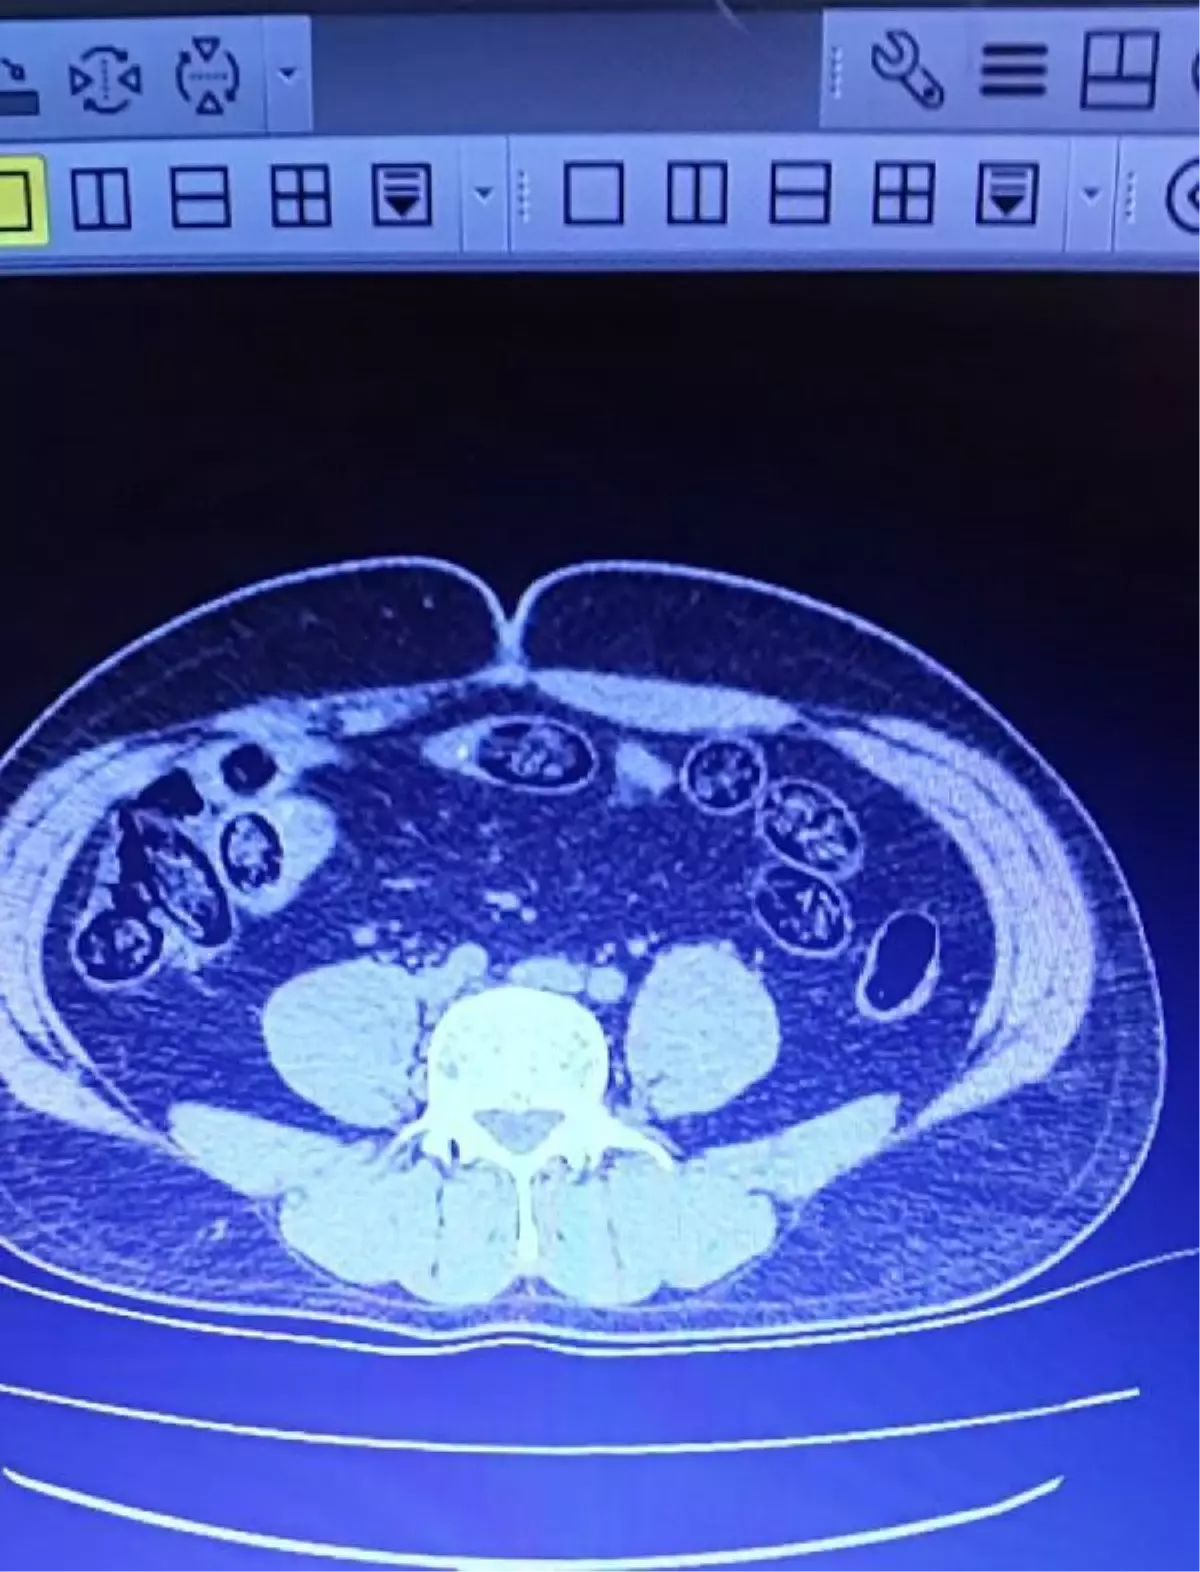

VAN'dan İzmir'e gitmek için Ferit Melen Havalimanı'na gelen 2 İran uyruklu, polis ekiplerince şüpheyle durduruldu. Üst araması sonrası iç muayene için hastaneye sevk edilen 2 kişinin midesinde, 103 kapsül halinde 920 gram metamfetamin tespit edildi.

?İl Emniyet Müdürlüğü Narkotik Suçlarla Mücadele Şubesi ekipleri, Van'dan İzmir'e gitmek için Ferit Melen Havalimanı'na gelen İran uyruklu 2 kişiyi şüphe üzerine durdurdu. Üzerlerinde arama yapılan ve uçağa binmeleri engellenen 2 şüpheli, iç beden muayene yapılması için hastaneye sevk edildi. Muayenede şüphelilerin midelerinde, 103 kapsül halinde 920 gram metamfetamin tespit edildi. Gözaltına alınan 2 İran uyruklu, sevk edildiği adliyede çıkarıldığı mahkemece tutuklandı.